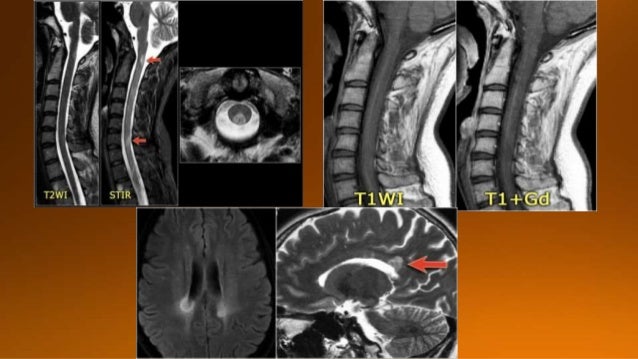

17. 17. NMO presenting with neuritis optica (arrows).The brain is normal

18. 18. One month later this child presented with acute transverse myelopathy, i.e. bilateral symptoms. The images show abnormal signal in the spinal cord with swelling and some enhancement. An astrocytoma could very well present with these images, but given the history of an optic neuritis and the acute myelopathy, we do not think of a tumor. This proved to be NMO and the Ig-test for NMO was positive.

19. 19. Previously it was thought that in NMO the brain was spared, but now we know, that brain lesions do occur. They are often distinct from those seen in MS. The location of the brain lesions in NMO is only around the ventricles.

20. 20. It is also possible to have large lesions in the corpus callosum of patients with NMO . So in any CNS disease with optic nerve and spinal cord involvement it is good to do the test for NMO-IgG.

21. 21. • Bilateral but typically asymmetric multifocal white matter lesions, with or without damage of the grey matter • Extensive disease of several spinal segments with expansion. • Low signal inT1 sequences • Well defined with a high signal inT2 sequences; gadolinium enhancement is variable. • All patients with spinal involvement have brain damage.